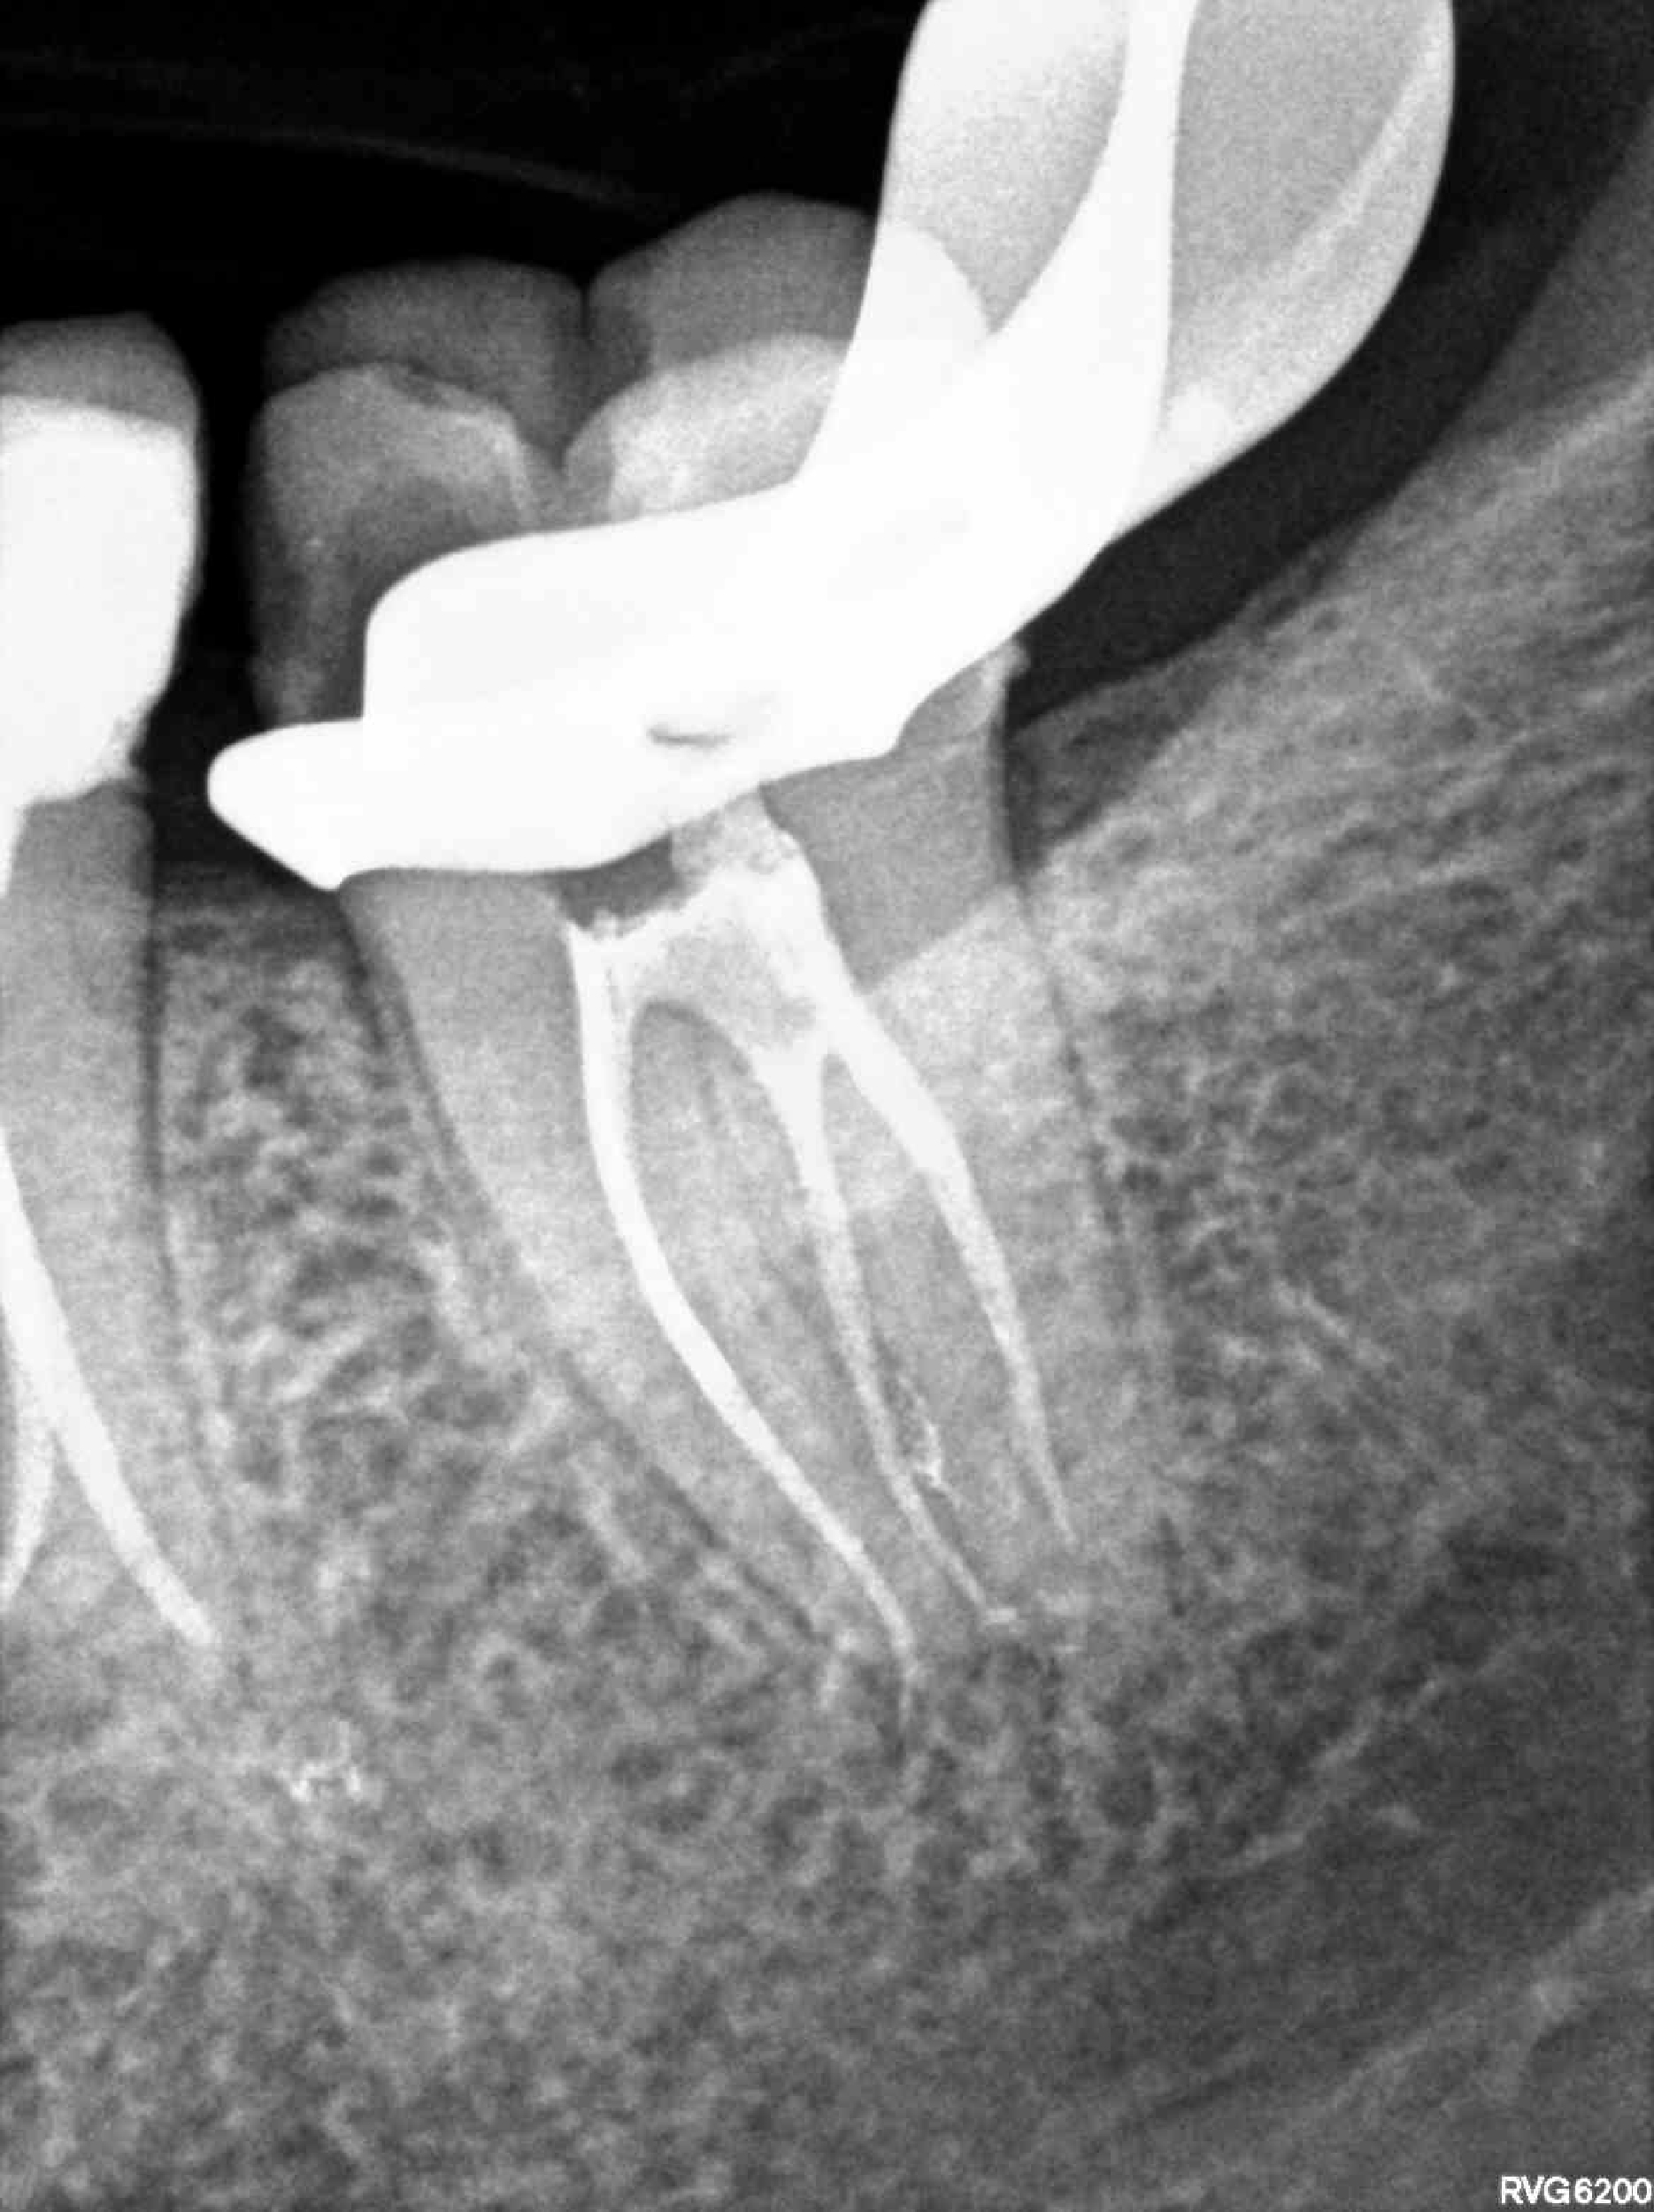

Principalmente me dedico a intentar salvar dientes a través de tratamientos endodónticos, todo tipo de intervenciones quirúrgicas relacionadas con la endodoncia: microcirugía apical, sellado quirúrgico de reabsorciones, amputaciones radiculares y últimamente autotrasplantes, reimplantes, extrusiones quirúrgicas parciales, todo esto con un enfoque mínimamente invasivo.

Soy perfeccionista y cuidadosa con los detalles, intento abordar los casos de una forma lo más conservadora posible con la estructura dental, aunque lleve más tiempo y sea más complejo desde el punto de vista técnico.

Últimos trabajos de especial complejidad relacionados con tratamientos de endodoncia, traumatología dental y microcirugía apical.